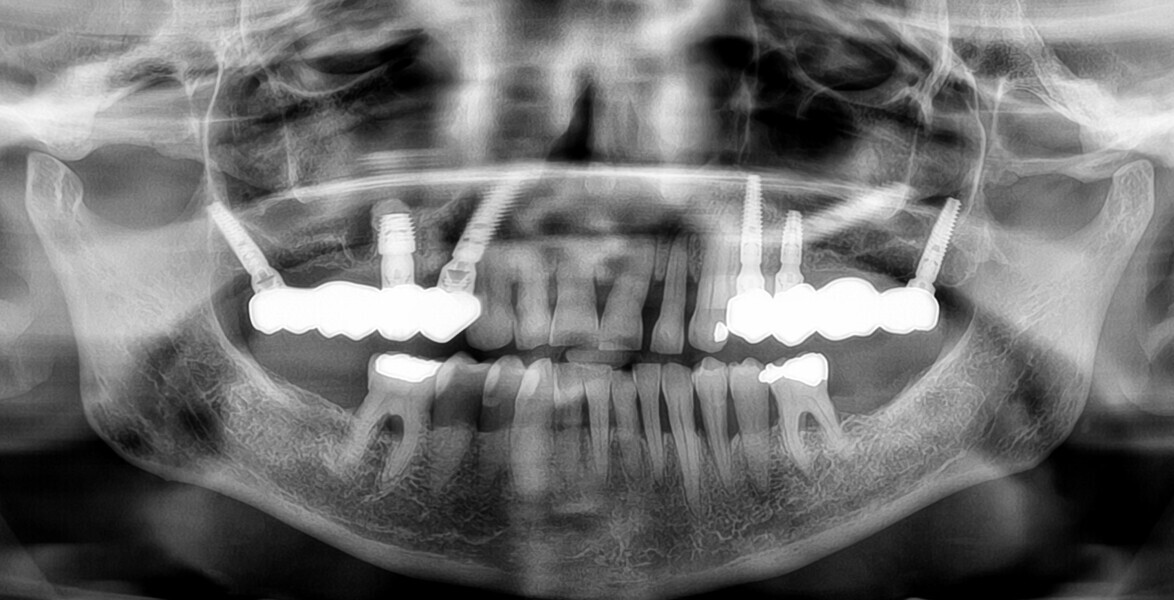

PrimeTaper EV implants (Dentsply Sirona) were placed in the maxillary premolar and molar positions (Fig. 2). MultiBase Abutments EV (Dentsply Sirona) were positioned and temporary screw-retained bridges loaded immediately (Figs. 3 & 4). To ensure that the implant positions were correct, a postoperative radiograph was performed (Fig. 5).